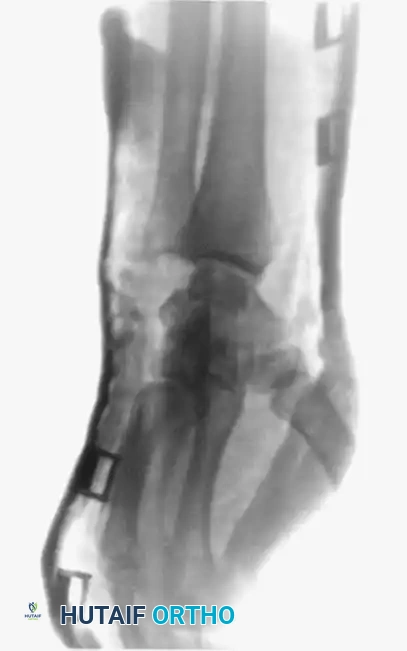

3. Plate and Screw Fixation

Short oblique, transverse, or highly comminuted fractures with unacceptable displacement require rigid stabilization with plate and screw constructs. Dorsal plating provides a strong biomechanical construct against the volar bending forces exerted by the intrinsic muscles.

Image

Care must be taken to limit periosteal stripping to preserve the fracture hematoma and blood supply. Low-profile titanium plates (1.5 mm to 2.0 mm systems) are preferred to minimize irritation of the overlying extensor tendons.

In cases of severe comminution or bone loss, bridge plating techniques can be employed to maintain length and rotation while secondary bone healing occurs.